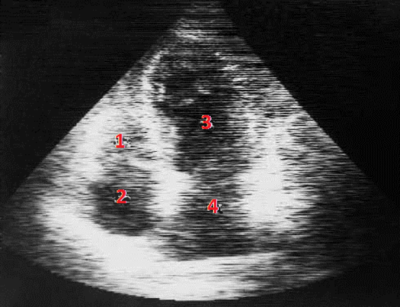

Ecocardiografía Doppler:

Hipertrofia del septo interventricular y del ventrículo izquierdo. Identifique según los números.

Answer

• Aurícula derecha, Ventrículo derecho, Aurícula izquierda y Ventrículo izquierdo.

• Ventrículo derecho, Aurícula derecha, Aurícula izquierda y Ventrículo izquierdo.

• Ventrículo derecho, Aurícula derecha, Ventrículo izquierdo y Aurícula izquierda.

• Aurícula izquierda, Aurícula derecha, Ventrículo izquierdo y Ventrículo derecho.